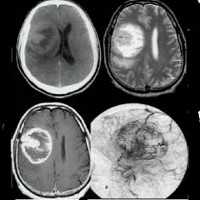

Компьютерная томография

При проведении компьютерной томографии вследствие высокой целлюлярности герминомы характеризуются гиперденсностью по сравнению с паренхимой головного мозга. Опухоль хорошо накапливает контрастное вещество.

При расположении на нижней стенке третьего желудочка опухоль заполняет его объём и простирается в инфундибулярный и супраоптический карманы. Радиологическая картина, однако, может быть нормальной, и если данный диагноз подозревается клинически (идиопатический гипоталамический несахарный диабет), необходимо более тщательное рассмотрение потенциального очень невыраженного аномального накопления контрастного препарата в воронке гипофиза и ее утолщение.

У детей наличие обызвествления в пинеальной области - полезный маркер данной опухоли, поскольку его отсутствие наблюдается только у детей моложе 6,5 лет и только у ~10% детей в возрасте от 11 до 14 лет.

Магнитно-резонансная томография

При МРТ герминома представляет собой мягкотканное образование, обычно овальной формы или дольчатой структурой, вытесняющее ткань эпифиза со следующими сигнальными характеристиками:

- Т1

- изо- или слегка гиперинтенсивные по сравнению с прилежащей тканью головного мозга

- может иметь множественные кисты

- может иметь участки кровоизлияний

- имеется предрасположенность к внедрению в соседние ткани (вызывая отек)

- центрально расположенная кальцификация проявляется гипоинтенсивной областью (смещённый эпифиз)

Следующим звеном в диагностике герминомы головного мозга является применение КТ и МРТ головного мозга. Томографические методы исследования позволяют установить опухолевый характер образования, его размеры и расположение. Примерно у 40% больных с герминомой головного мозга выявляется характерный для этой опухоли признак — опухолевая инфильтрация зрительных бугров и наличие расположенного в середине петрификата (симптом бабочки). В пользу герминомы могут говорить распространение опухолевого процесса по боковым желудочкам и метастазирование в инфундибулярную область III желудочка.